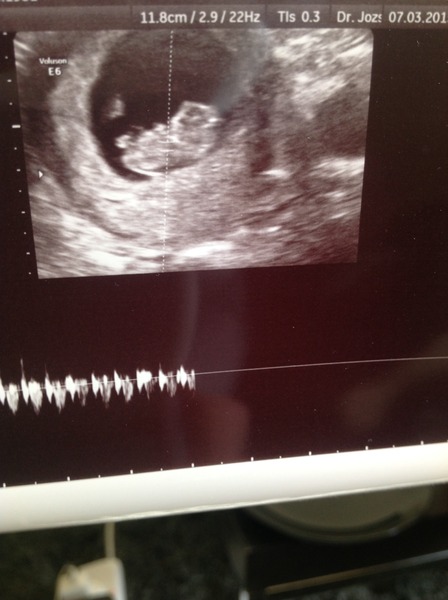

batfish · 07/03/2015 12:18

Baby bat!

Great scan Bat, congrats!